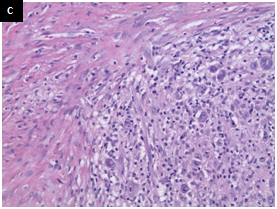

The H&E stained sections showed a dense dermal infiltrate without epidermotropism. The epidermis was ulcerated but otherwise unremarkable. The dermal lesion showed a diffuse, infiltrative growth pattern with some necrosis (Figurers 1a & 1b). Tumor foci are not surrounded by rim of small lymphocytes (Figurers 1b & 1c). At high magnification, it consisted of scattered large atypical cells in a background of mixed inflammatory cells including small lymphocytes, plasma cells, neutrophils and rare eosinophils. The atypical cells demonstrated large nuclei with vesicular chromatin, prominent inclusion-like nucleoli and ample amphophilic cytoplasm. Some of them had bilobed mirror-image nuclei. The large atypical cells were morphologically consistent with Hodgkin/Reed-Sternberg (HRS) cells and their variants (Figure 1c & 1d). Frequent mitotic Figureures, including atypical forms, are also noted (Figure 1d).

Figure 1 A. Low-power view shows a diffuse, dense dermal infiltrate with some necrosis and overlying ulcerated epidermis. B. Tumor cells demonstrate an infiltrative growth pattern, without a surrounding rim of small lymphocytes. C. The large cells are present at the base of the lesion, without a surrounding rim of small lymphocytes. D. High-power view shows large atypical cells in a background of mixed inflammation. The large cells have prominent eosinophilic nucleoli. Some of them are binucleated or multinucleated. The morphologic features are consistent with Hodgkin/Reed-Sternberg (HRS) cells and their variants. Frequent mitotic figures, including atypical forms, are noted. (H&E, A and B 20X, C 200X, D 400X).